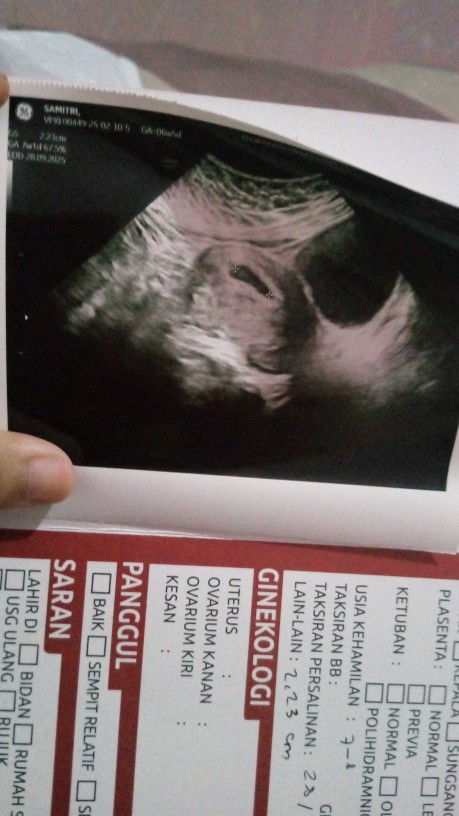

Yg hpl 5 Oktober sudah USG kah?? Alhamdulillah kmren sudah USG posisi plasenta yg tadinya di bawah sudah agak naik ke atas jknya juga sudah jelas Alhamdulillah laki laki 🥰🥰 Sharing yu yg sudah USG Dan apa nih keluhannya di setengah jalan ini Kalo saya tiap dingin batuk ga berenti kadang sesek lapar terus tapi di isi perut kaya mau meledak #Sharingdong_Bund #sharing #ingintahu